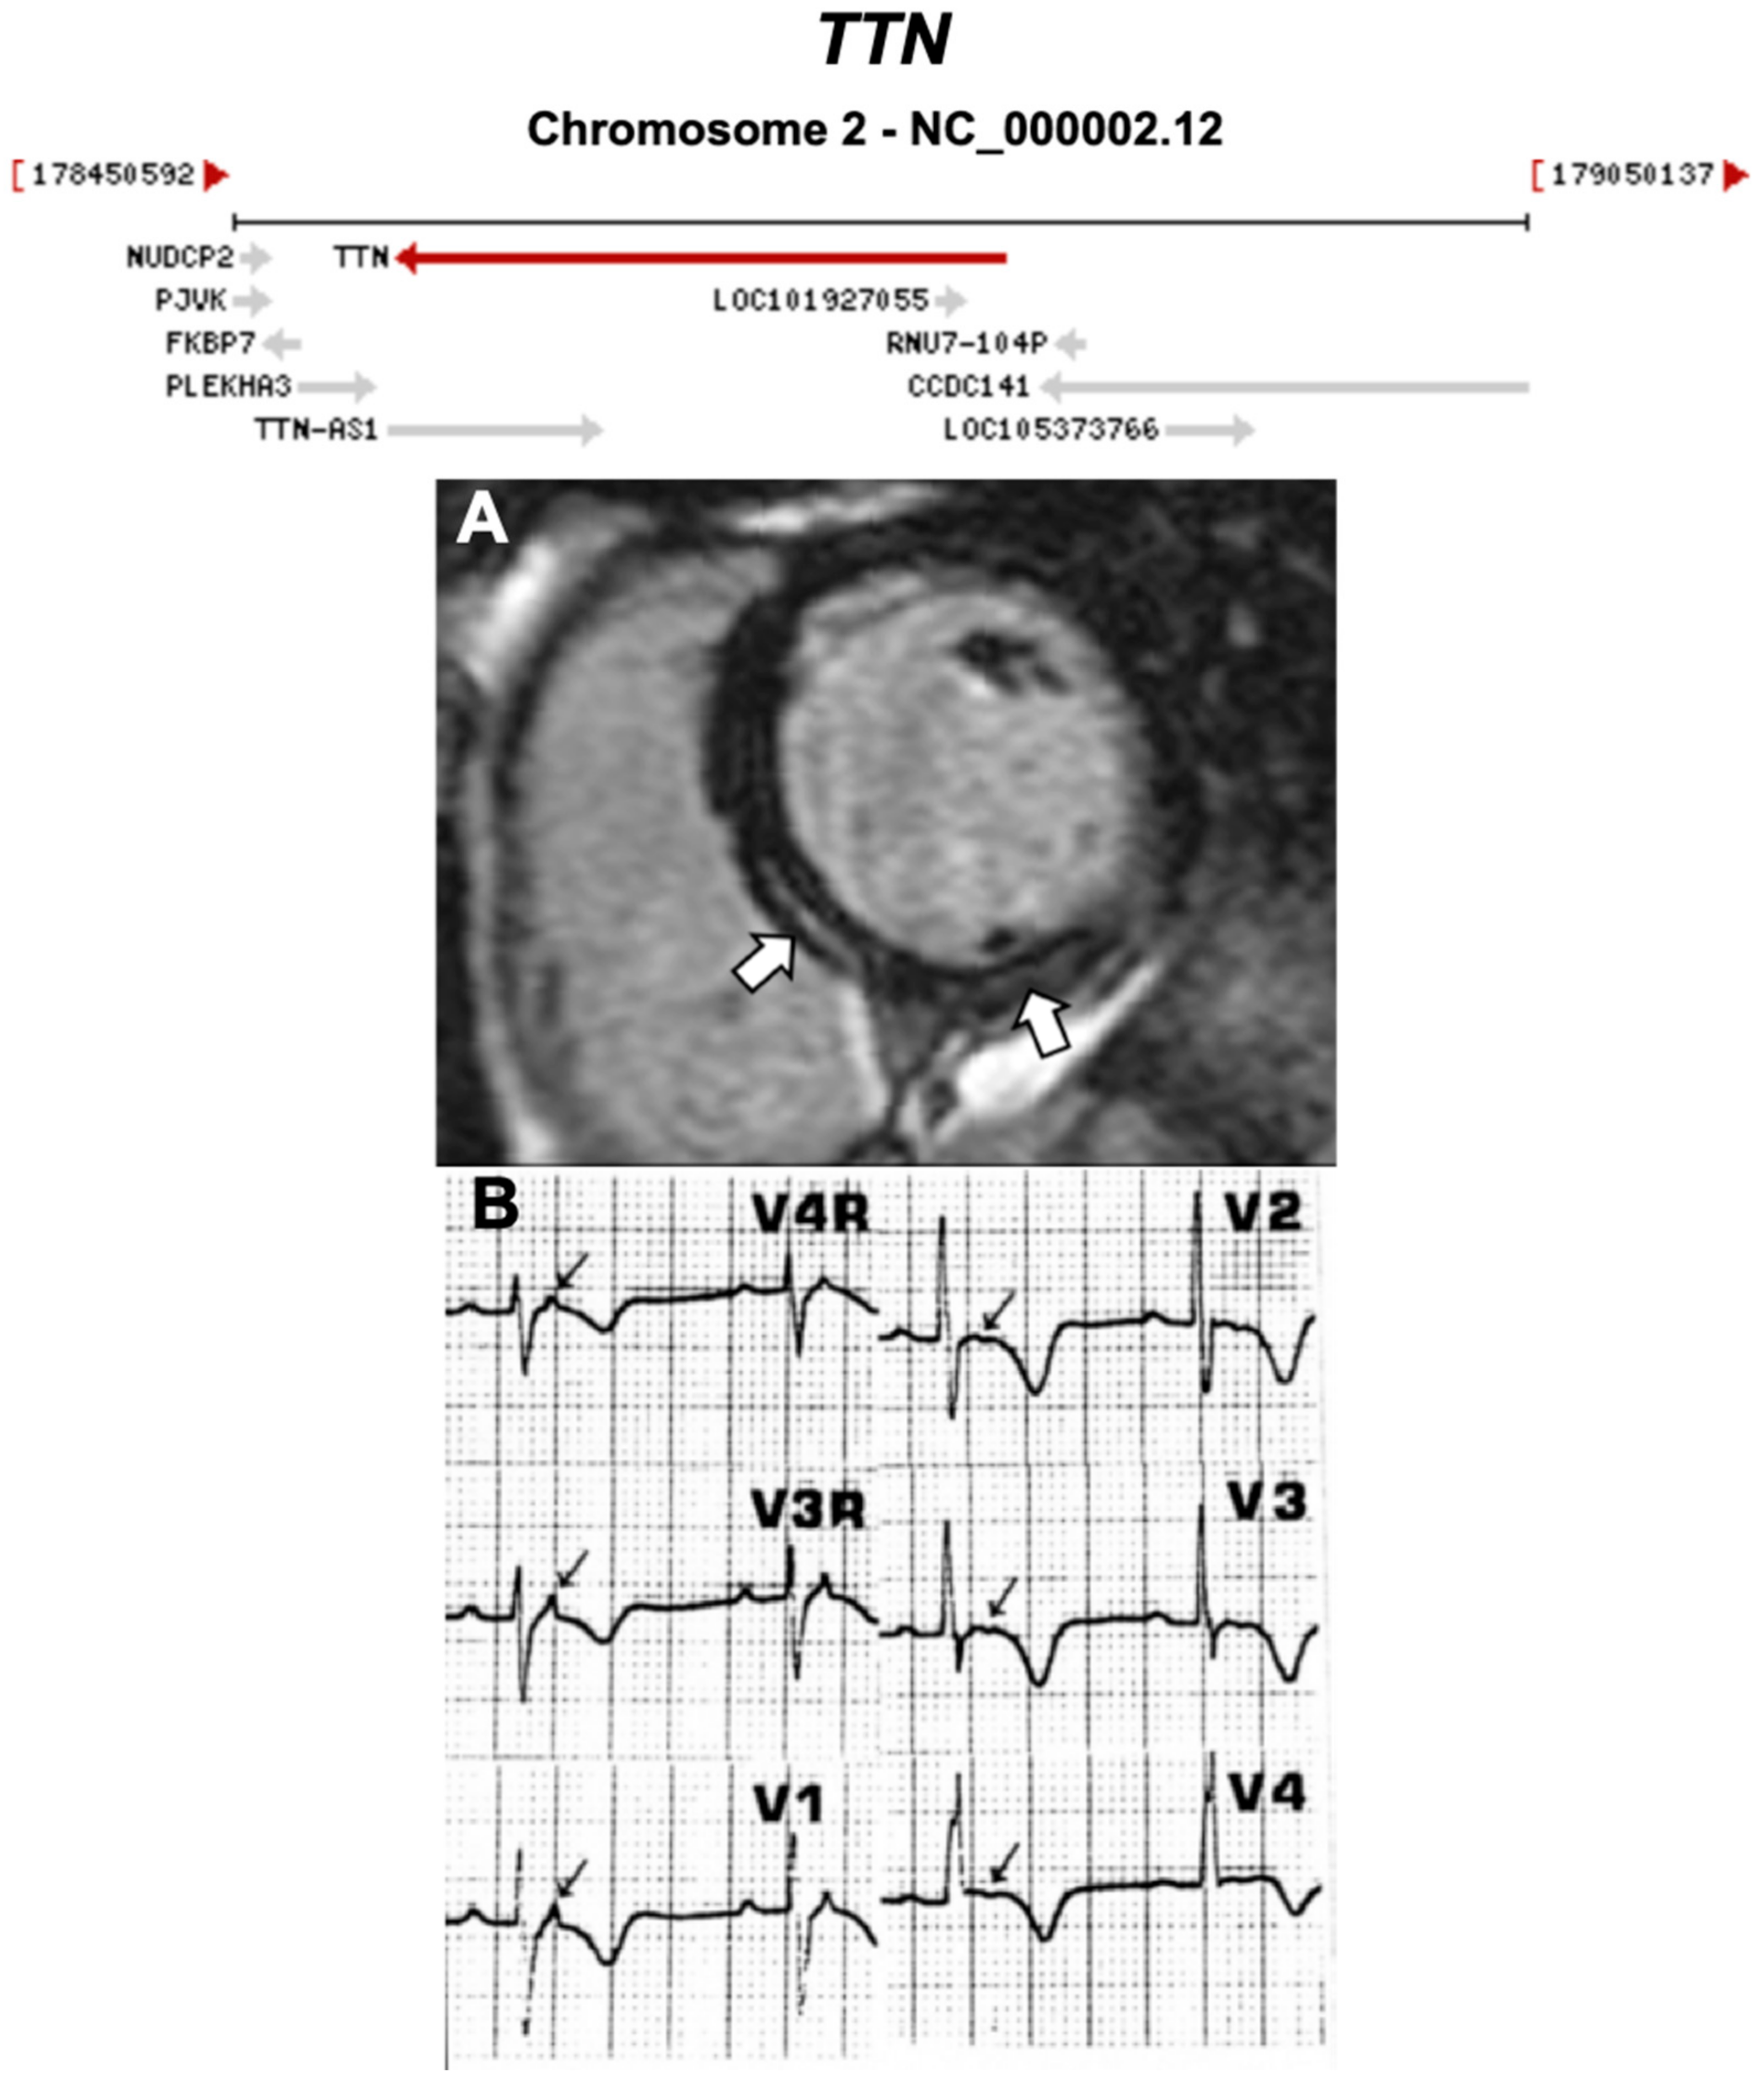

Figure 9.

Exemplar MRI and ECG finding found in ACM patients with TTN mutations. (A) CMR of a patient with TTN mutation, the white arrows show mid-wall scars in the inferior septum and inferior wall; (B) ECG of a different patient with TTN Thr2896Ile mutation showing epsilon waves. (A) was reproduced from Augusto et al. (2019) [39]; (B) from Taylor et al. (2011) [40] with permissions.